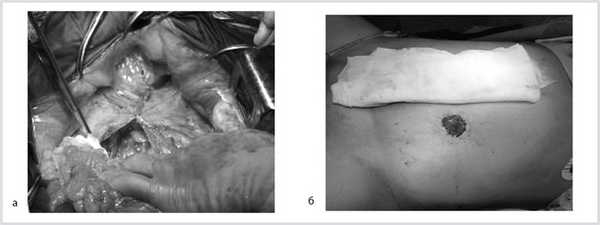

07.11.2012 выполнена цилиндрическая или экстралеваторная экстирпация прямой кишки. Через тазовую брюшину в мезоректальной клетчатке справа пальпируется верхний полюс опухоли, подрастающей к стенке прямой кишки, опухоль фиксирована к правой боковой стенке таза. Отдаленных метастазов нет (рис. 4).

Рис. 4. Этап операции. Ревизия опухоли.

Далее прямая кишка с опухолью в едином блоке мобилизована острым путем от предстательной железы и правой стенки таза, после чего выполнена цилиндрическая брюшно-промежностная экстирпация прямой кишки. Малый таз дренирован двумя силиконовыми дренажами и ушит наглухо (рис. 9).

Рис. 9. Этапы операции. а — мобилизация простаты; б — дренирование малого таза; в — конечный вид раны.

Гистологическое заключение: в жировой клетчатке прямой кишки, с учетом иммуногистохимического исследования разрастания злокачественной гемангиоперицитомы с признаками лечебного патоморфоза 1-й степени (жизнеспособной опухолевой ткани более 50% по DWORAK). Опухоль не прорастает в прилежащий мышечный слой кишки. В одном лимфатическом узле прилежащей клетчатки элементов опухолевого роста нет. В краях резекции кишки без элементов опухолевого роста. Под маркировкой «латеральный край опухоли» — кусочек фиброзной ткани с очагами ксантоматоза (рис. 10).

Рис. 10. Макропрепарат.

Продолжительность операции составила 3 ч 30 мин, кровопотеря — 500 мл. Интраоперационных и ранних послеоперационных осложнений не было. Пациент на 12-е сутки выписан из хирургического отделения.